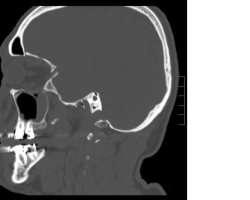

- TDM sans injection en coupes axiales, coronale et sagittale

Fracture du plancher orbitaire, du toit de l’orbite, de la paroi temporale. - Photos